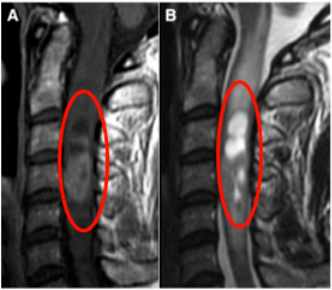

然而近一个月,情况却和之前有所不同。肩颈的疼痛越发难以忍受,疼痛甚至使其难以入睡。同时出现上肢麻木、无力情况。预感不妙的她赶紧去医院检查,然而万万没想到竟然是“脊髓髓内室管膜瘤”(图A)在作祟。

不仅如此,延髓也出现广泛水肿(图B)。“什么是脊髓髓内室管膜瘤?”明明简单以为是颈椎病为何会发展为脊髓的肿瘤,应该怎么治疗?可以治好吗?Emma的脑子里有无数疑问。